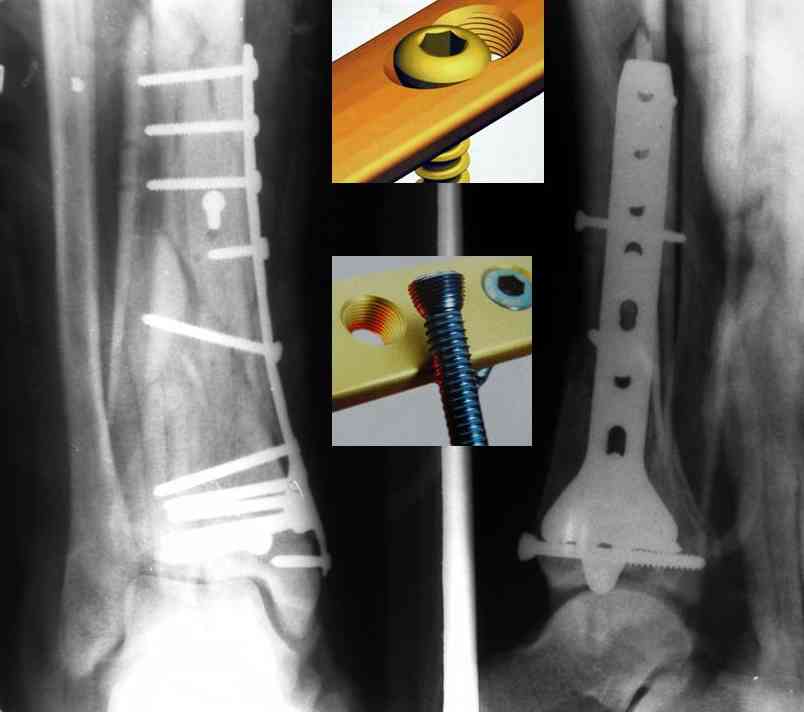

На рентгенограммах типичный перелом пилона по типу С-3. есть опыт до 100 открытых опреаций у нас в клинике. 20 примерно в год. Принцип один -все внутрисуставные переломы нуждаются в открытой репозиции и внутренней стабильной фиксации. При поступлении КТ не надо, так как получается только нагромождение костей. Истинной картины нет. Главное восстановить длину малоберцовой кости - это ключ к успеху. При поступлении меньше всего надо думать о сосудистых расстройствах, т.к. сама операция и репозиция даже сначала частичная даёт улучшение сосудитых нарушений. Причём очень быстро. Операция в 2этапа. При поступлении доступ позади наружной лодыжки, причём обязательно. После этого репозиция малоберцовой кости и фиксация пластиной 1/3 трубки под винт 3,5. Дренаж и любой аппарат наружной фиксации. Затем после спадения отёка на 5-7-10 день аппрат снимается и дугообразный разрез спереди от медиальной лодыжки 10-12 см. Главной чтобы расстояние между 1 и вторым разрезом было не меньше 7-8 см. Тогда не будет некрозов лоскутов. Таранная кость используется как матрица на неё укладываются отломки и фиксируются пицами. Ренг-контроль. Отломки лежат все отдельно, но ничего не высыпется. При переломах С-3 всегда нужна костная пластика (из крыла). Фиксация пластиной лист клевера простой или LCP. Гипс не нужен. Дренаж до 48 часов. Операция длится 3-4 часа обязательно без жгута. Посылаю примерно такой же случай.

Кстати, при переломах переднего края по классификации АО В-3 при переломах пилона пластина укладывается по передней поверхности. Она достаточно тонкая и эластичная, не надо этого бояться. Посылаю три снимка.